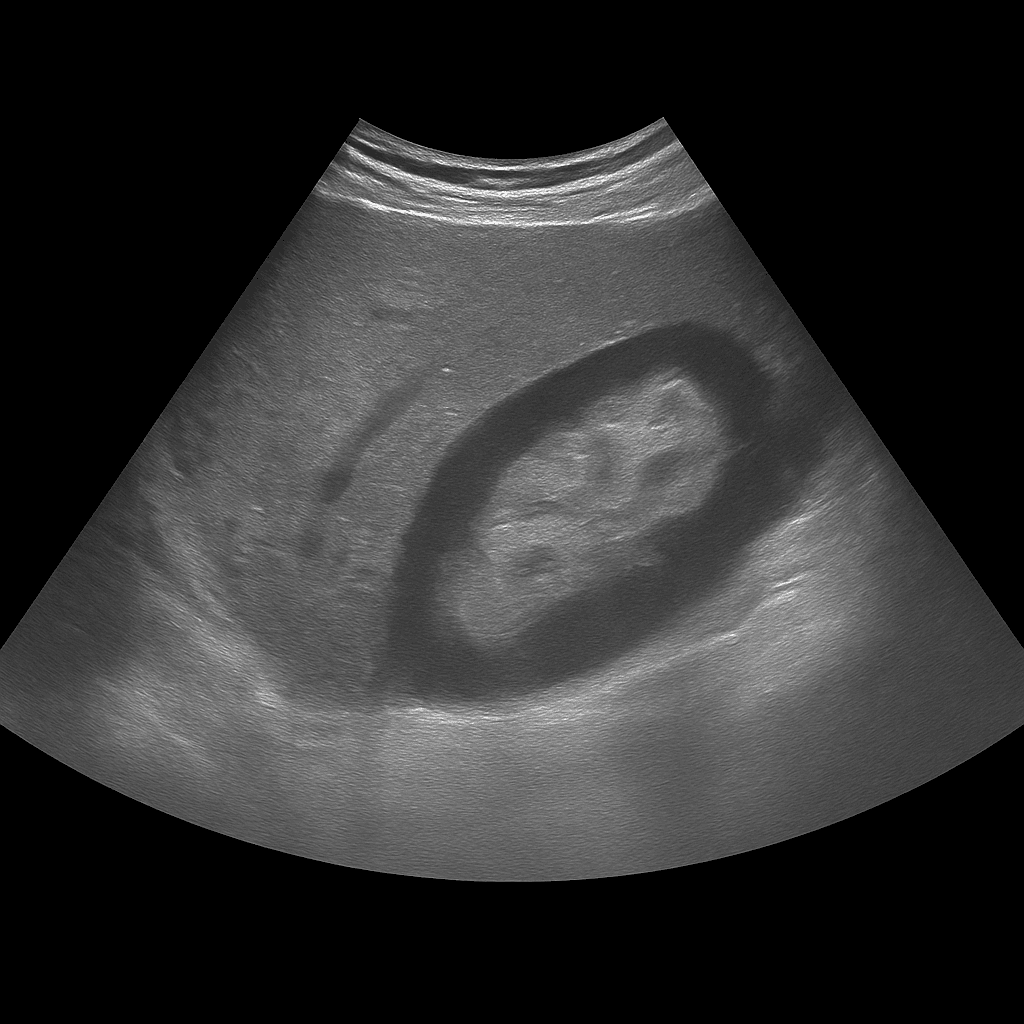

A kidney ultrasound is used to examine the size, shape, tissue structure and blood flow of the kidneys. The examination is performed by a specialist in radiology and provides detailed images in real time that can detect changes that affect kidney function or urine flow. It is used to investigate, among other things, kidney stones, cysts, fluid accumulation, infections or suspected tumors.

Unlike MRI and CT, which are often used for more advanced mapping or suspected tumors, ultrasound is the first-line method for functional and structural assessments. It can be performed without contrast media and shows the kidneys in real time – ideal for detecting stones, cysts or fluid accumulation without the risk of radiation.

The examination is performed while you lie on your back or side. A gel is applied to the skin and the doctor moves the ultrasound probe over the area where the kidneys are located. Both kidneys are assessed in longitudinal and cross-sectional views, and if necessary, the bladder is also examined to assess any impact on urine flow. The examination is painless and usually takes 15–20 minutes. You do not normally need to fast or prepare, but sometimes the doctor may ask you to drink water before the examination so that the bladder is slightly full.